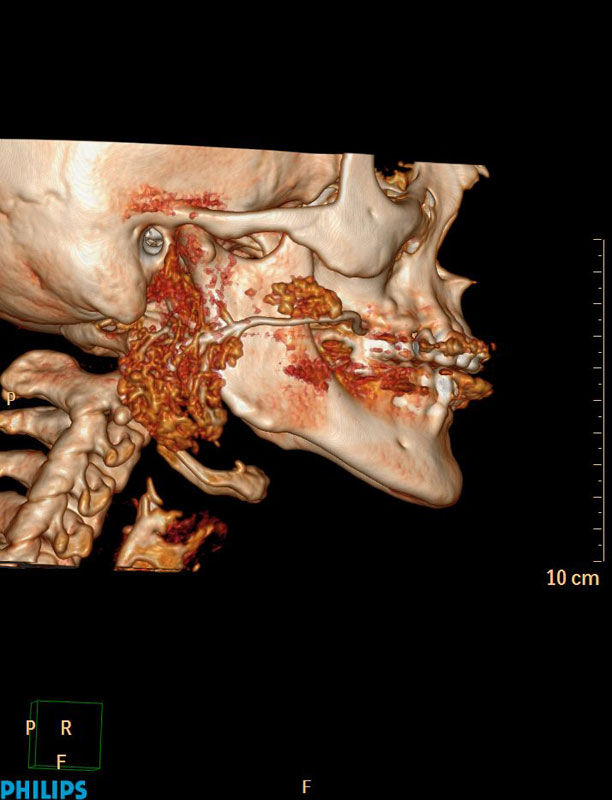

Апробированы современные методики в диагностике заболеваний слюнных желез, которые позволяют с высоким пространственным разрешением и возможностью построения 3D реконструкций оценить наличие нарушения проходимости протоков слюнных желез